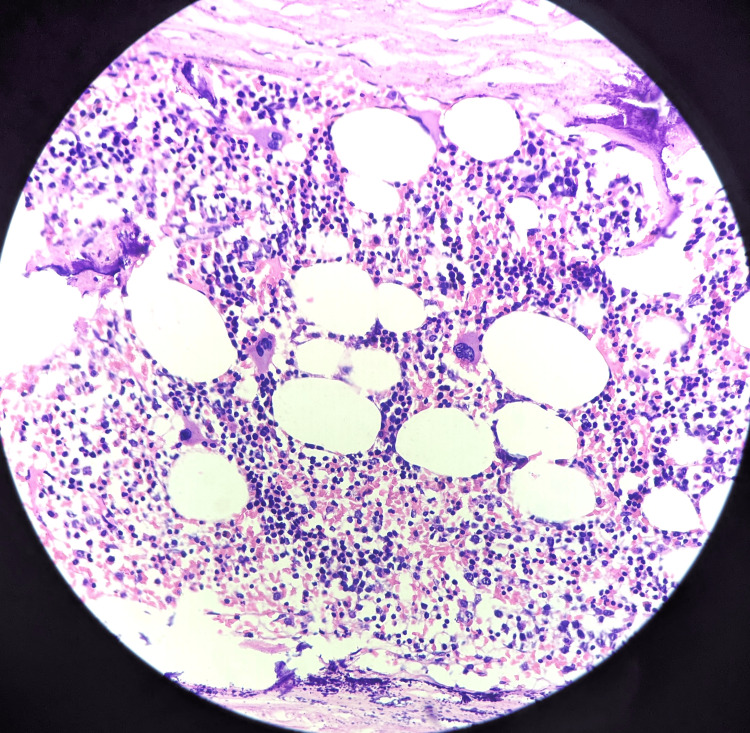

Microscopic examination of the specimen showed bone marrow hematopoietic elements and mature adipocytes (Figure 4) undergoing necrosis ensheath by capsule with foci of dystrophic calcification beneath the affected residual kidney (Figure 5).

Figure 4. Microscopy showed bone marrow hematopoietic elements and mature adipocytes (40x magnification).

Haematoxylin and Eosin (H&E) stain was used